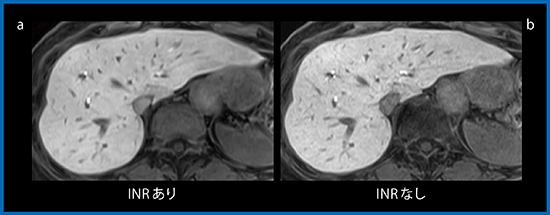

さらに,ノイズ低減技術として新たに開発されたのがiterative noise reduction(INR)法である。INR法は,パラレルイメージングの展開図に算出したノイズレベルのg-factorを繰り返し再構成の過程でパラメータとして与えることにより,g-factorの高い領域のSNRを改善する技術である。

症例2(71歳,女性)では,INR併用の画像でノイズが減少していることが確認できる(図4 a)。

図4 症例2:HCC(71歳,女性)の肝細胞造影相

腹部領域において,TRILLIUM OVALは安定した画像の撮像が可能である。特にEOB造影MRIで使用するTIGREシーケンスは,動脈相においてHCCの血流を正確に評価できる可能性がある。また,INRはSNRを向上させることで,肝細胞造影相の画質を改善することができる。腫瘍性病変の検出能向上も期待でき,今後検討していきたい。